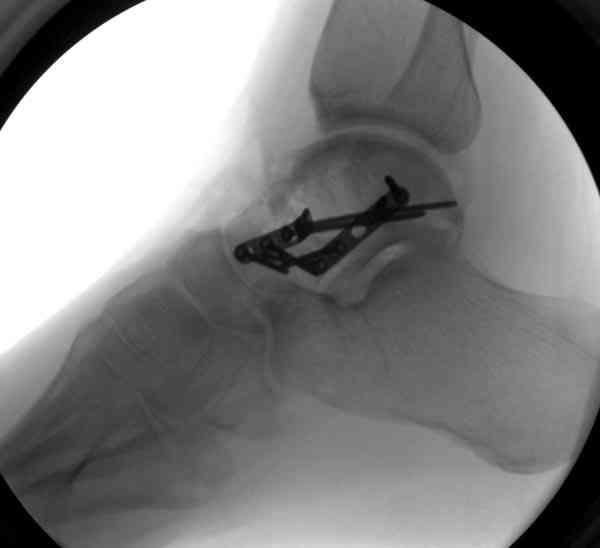

При в первом типе придерживаемся закрытой репозиции, а у всех остальных в зависимости от смещения предпочитаем открытую репозицию, фиксация шурупами или пластиной. Пластина 2.4 мм более предпочтительна для удержания мелких костных осколков.

В вашем случае доступ через перелом медиальной лодыжки, обычный доступ через остеотомии лодыжки, где имеется возможность прямой репозиции тарана, после фиксации шурупами, лодыжки фиксируются обычным 2х лодыжечным методом.

Случай с множественным оскольчатым переломом тарана оперированный из двойного доступа.

На ренгенограмме не уловил многоскольчатость тарана, чтобы доказать, конечно, можно было исследовать на КТ, потом КТ дает ориентацию фрагментов.

Два фрагмента суставной поверхности тарана можно восстановить боковой компрессией шурупами и дополнительно костная пластика.

(кстати, на нашем случае была применена костная пластика-allograft crouton для заполнения дефектов)